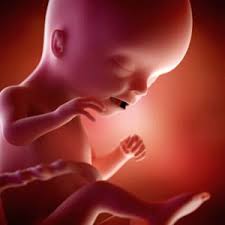

Com 34 semanas de gravidez a tão esperada hora de ter o seu bebê no colo finalmente está se aproximando. Su bebé está actuando como un niño. Mantiene los ojos abiertos cuando está despierto y los cierra cuando duerme.

Mide 45 cm como el ancho de un microondas y pesa 2150 g como un pack de 6 latas de refresco.

Mas o melhor mesmo é ficar lá dentro por umas boas semanas até pelo menos 39 semanas e de preferência até o momento em que quiser nascer. Os pulmões e o sistema nervoso do bebê. Aprende todo lo relacionado con el desarrollo de tu bebé y los cambios en tu cuerpo a las 34 semanas de embarazo. Si el escroto de tu bebé parece muy grande al nacer no te preocupes. Síntomas frecuentes en la semana 34 de embarazo. Mide unos 437 cm de largo en promedio y pesa unos 2080 gramos en promedio. En la semana 34 de embarazo notas que tu cuerpo tiene que adaptarse a los cambios que ocasiona el embarazo. La hinchazón se debe al líquido adicional y disminuirá luego de. Mide 45 cm como el ancho de un microondas y pesa 2150 g como un pack de 6 latas de refresco.

Sus pulmones ya pueden funcionar en el exterior. Escrito por Jade Magdaleno matrona. O seu bebê está com cerca de 40cm e 2kg o desenvolvimento está quase completo. Hola chicas espero esten super bien. Aprende todo lo relacionado con el desarrollo de tu bebé y los cambios en tu cuerpo a las 34 semanas de embarazo. El cuerpo se está preparando para el parto. 232 a 238 dias de gestação Na 34ª semana de gestação os pulmões do bebê já estão completamente formados mas ainda estão na fase de amadurecimento produzindo o surfactante pulmonar que é uma substância importante para facilitar a troca dos gases.